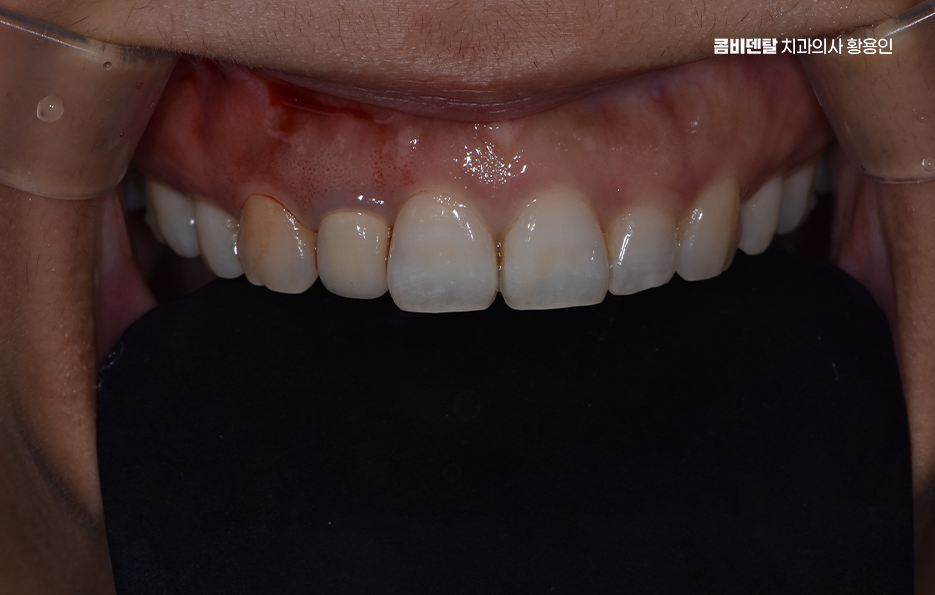

출처 아카이브 열기앞니에 문제가 생기리라고는 생각도 못 했어요. 보통 어금니 쪽이 먼저 약해지고, 충치가 생기고, 크라운 치료를 하게 된다는 말을 많이 들었기 때문에, 앞니는 보통 칫솔질이 어렵진 않으니까 오래 갈 거라는 막연한 믿음 같은 게 있었어요. 그런데 어느 날 양치질을 하다가 앞니 한쪽 끝이 조금 갈라진 걸 우연히 발견했고, 처음엔 그냥 마모 정도로 여겼어요. 하지만 시간이 지나면서 뭔가 이상하다는 생각이 들었고, 결국 치과에 가게 되었어요. 앞니라서 더욱 조심스러웠는데, 결국 크라운을 해야 한다는 말을 들었을 때는 아무래도 걱정부터 들었어요

이처럼 보통 치아는 충치로 인해 손상된다는 인식이 있다보니 칫솔질이 잘 되는 앞니 손상에 대해서는 방심하는 경우가 많지만 생각보다 많은 분들이 앞니 충치를 겪기도 하고 앞니는 치아도 얇기 때문에 깨지거나 부러지는 일도 생각보다 많이 발생되고 있는데요

앞니는 사람의 얼굴에서 먼저 눈에 띄는 부위이기 때문에 심미적인 부분이 아주 중요한데 충치가 심하거나 깨지거나, 색이 변해버린 앞니를 그냥 두기에는 부담스럽고, 치료를 하더라도 주변 치아와 똑같이 자연스럽게 보여야 하다보니 이런 앞니에 적합한 보철치료 방법이 바로 앞니 올세라믹 크라운 치료라고 할 수 있어요